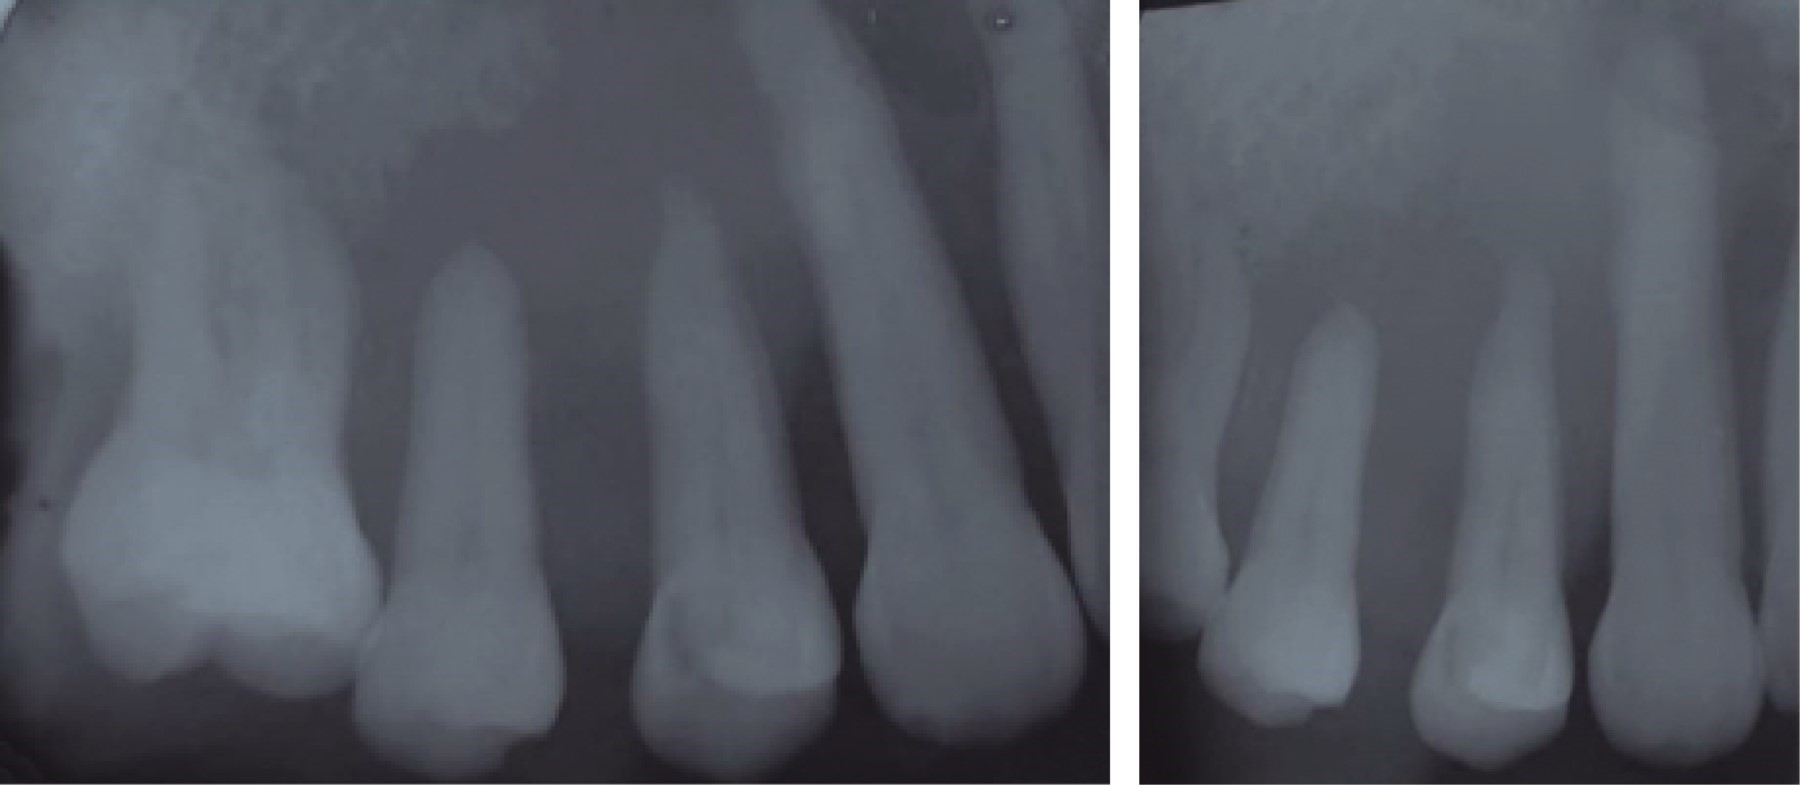

Oral squamous cell carcinoma of the palate: a case report.

Oral cancer represents a serious health problem worldwide due to its significant morbidity and mortality, it is the sixth leading cause of cancer death and has a global 5-year survival rate of 50%, largely due to the lack of recognition in early stages by patients and health professionals themselves, which causes a serious delay in diagnosis and treatment. We present the case of a 64-year-old woman with long-standing ulcers in the oral cavity who went to multiple health professionals without being diagnosed in the initial stages of the disease. She went to the Autonomous University of Tlaxcala where oral squamous cell carcinoma (OSCC) in the maxilla was diagnosed. This article emphasizes the recognition of clinical signs and precipitating factors that may generate suspicion of malignant growth and thus raise awareness among health professionals to promote prevention.

Figure 3